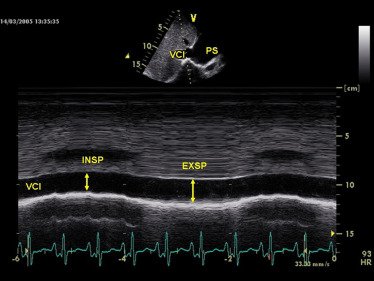

But CAD doesn't only affect the left ventricle.

Right ventricular infarction can occur, especially with right coronary artery occlusion.

Echo findings may include:

🔵 RV wall motion abnormalities

🔵 Reduced TAPSE

🔵 RV dilation Calculation of fractional area change (FAC) from tracings of end-diastolic area (EDA) and end-systolic area (ESA) of the right ventricle.

Image

Dilatation and loss of respiratory diameter changes of vena cava inferior visualized by using the M-mode method from subcostal view.